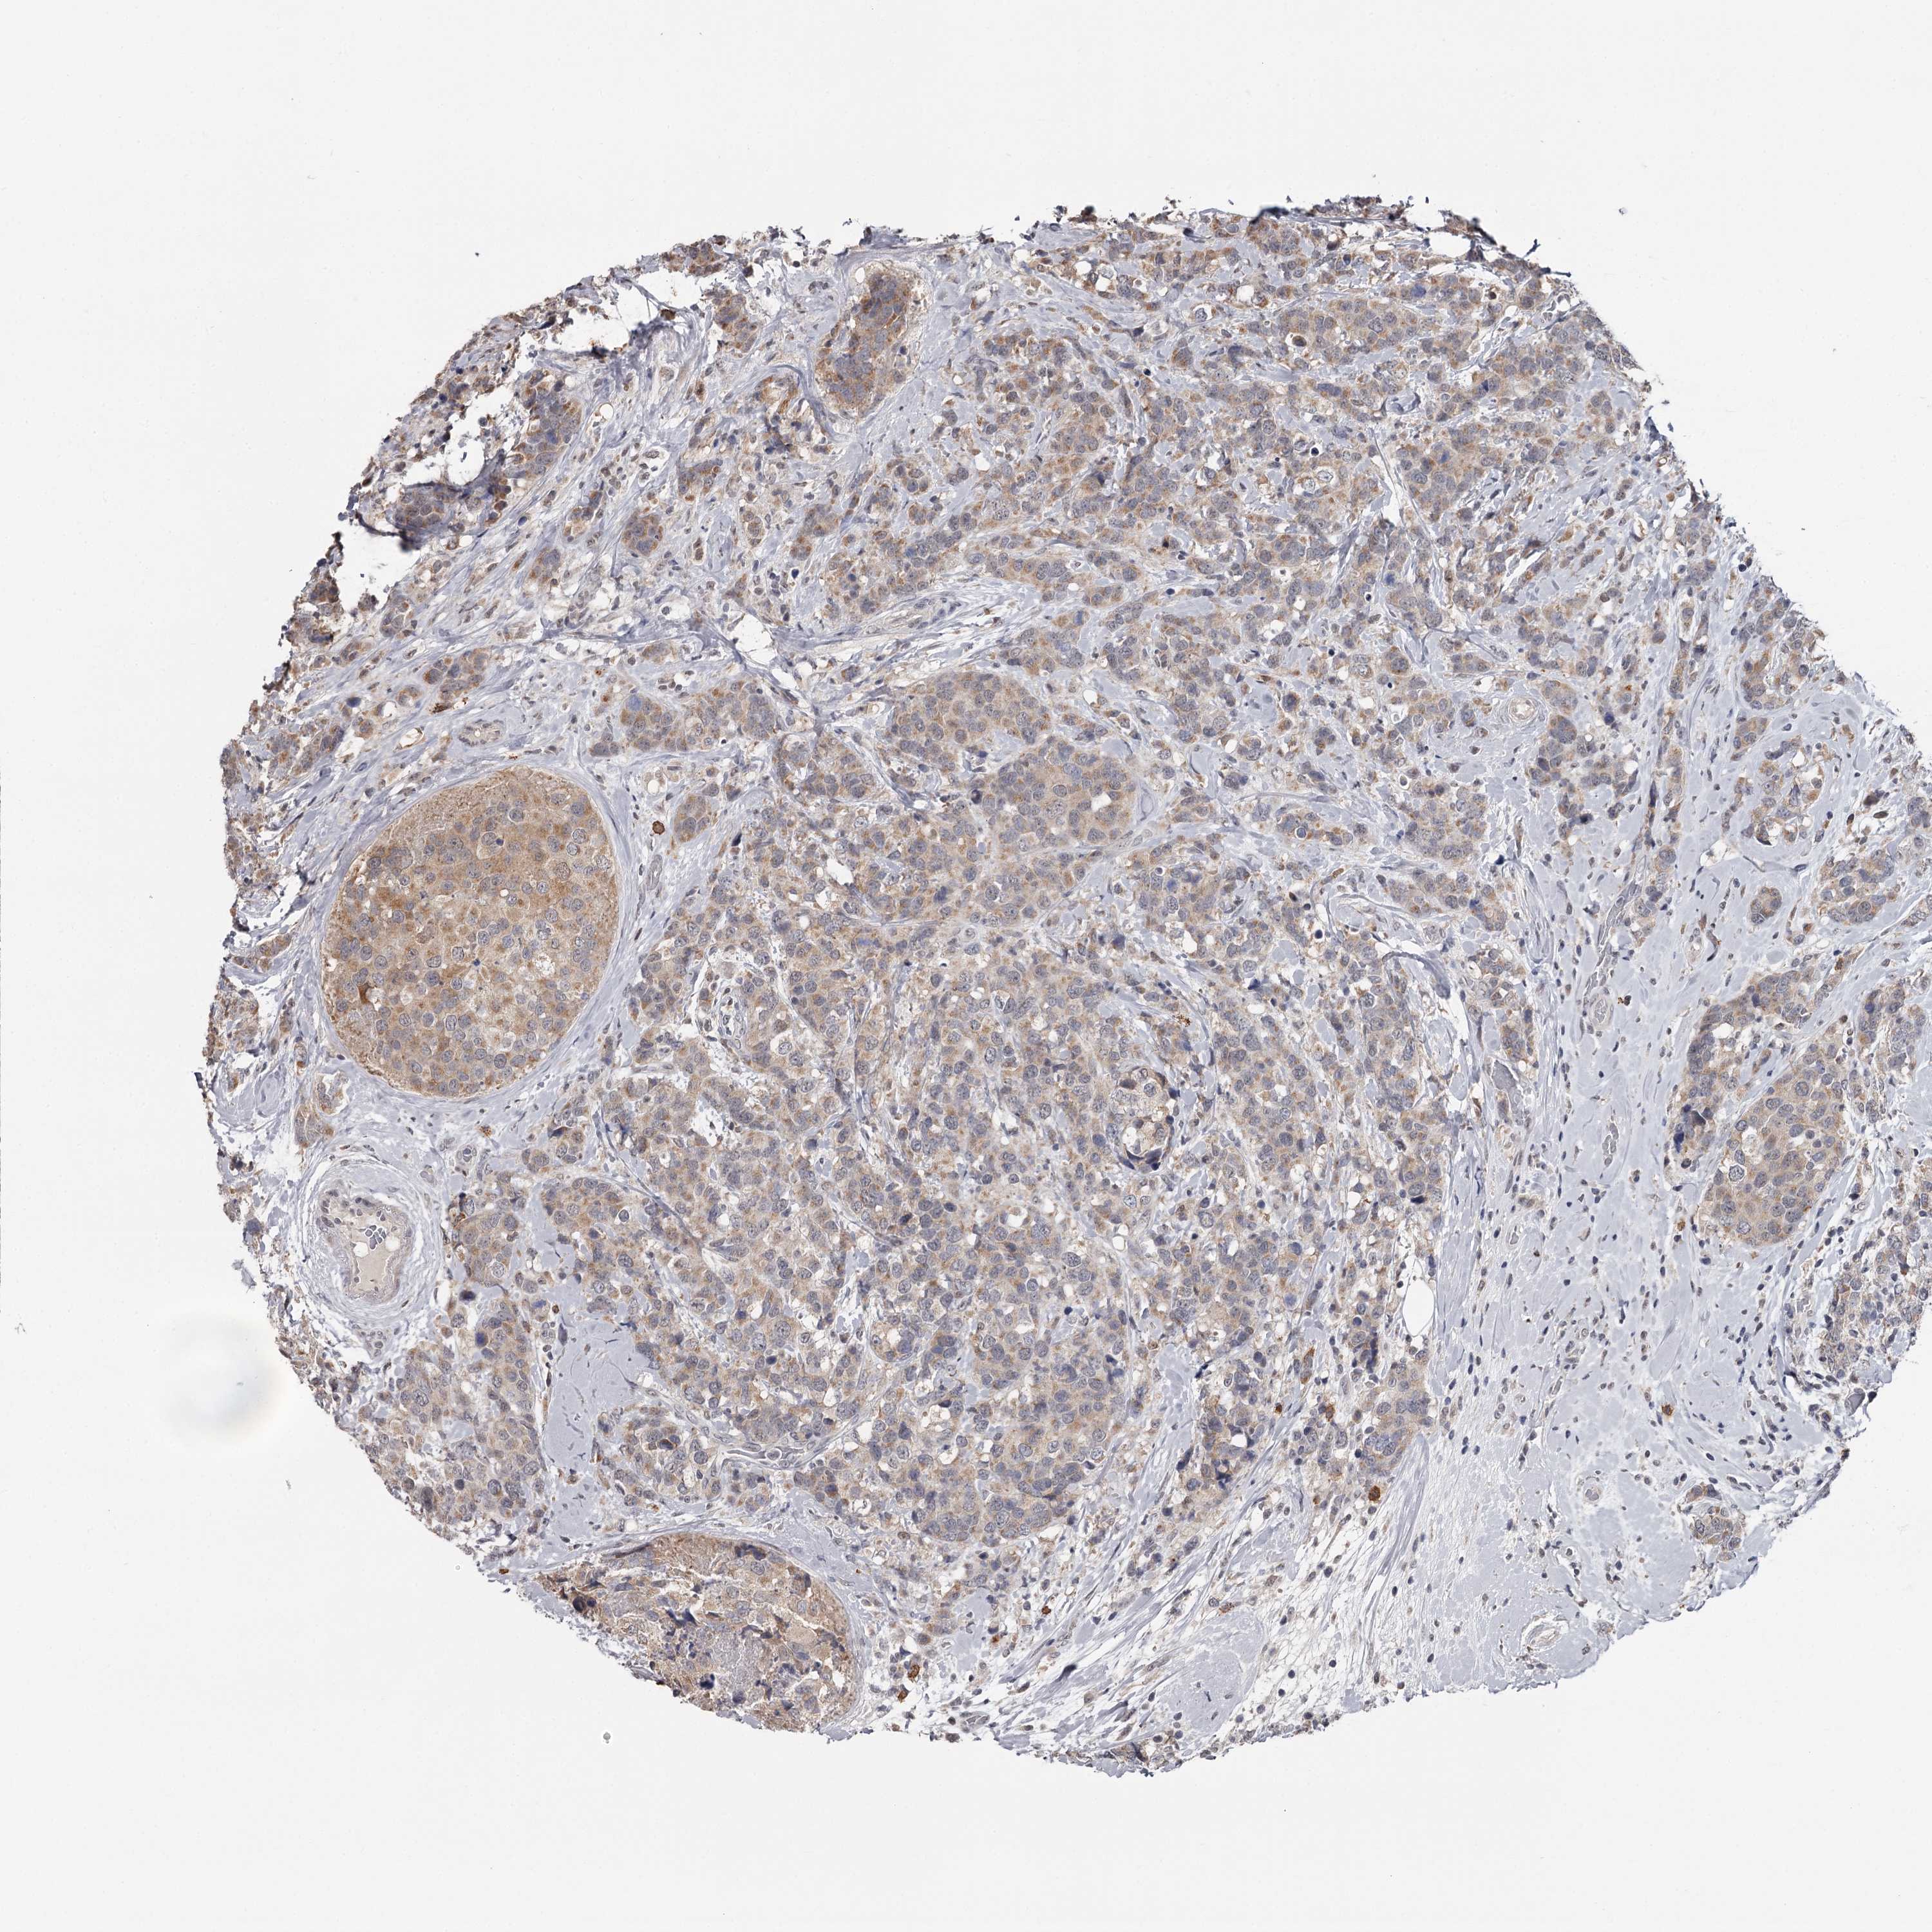

CANCER BREAST CANCER Show tissue menu

BRCA TCGA BRCA VALIDATION PROTEIN EXPRESSION